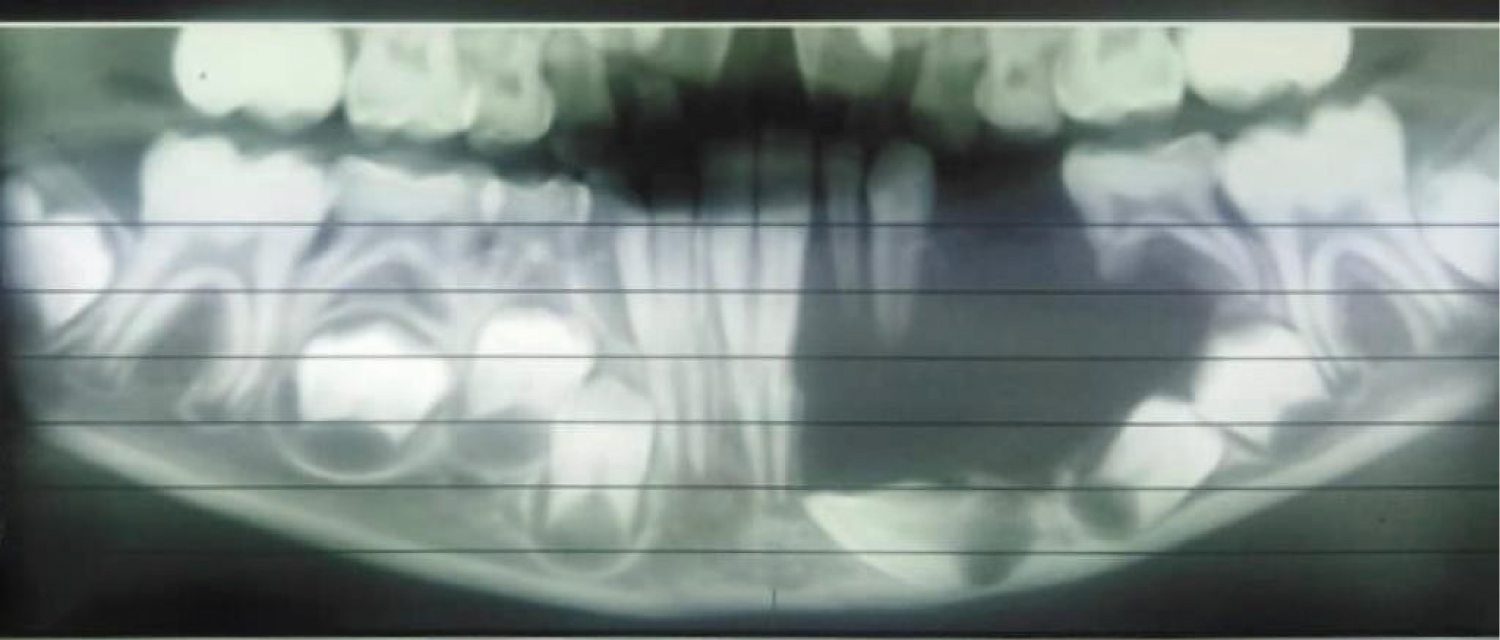

An 8-year-old African descent boy presented to the department of oral and maxillofacial surgery at Sharque Alnil Hospital complaining of swelling and lost teeth on the left side of the lower jaw for three weeks. No history of pain fever, loss of weight or night sweats. On examination, the face was symmetrical and no palpable lymph nodes. Intraorally, expansion of buccal and lingual cortices was seen on the left side of the lower jaw at the area of A, B, C, D, and E deciduous teeth with grade 2 motilities of A, B, C and D teeth and loss of tooth number D. no occlusal interference, no ulceration on the overlying mucosa. On the radiographic image (Figure 1 and Figure 2) Ill-defined radiolucency in the lower left side of the jaw extending from the first deciduous incisor to the second deciduous molar was evidence, permanent successors were within the tumor and were pushed downward and the lower border of the mandible was intact. In differential diagnosis, dentigerous or periapical cysts were thought. A biopsy was taken which microscopically showed interlacing bundles of oval cells with adjoining fibro-collagenous connective tissues and reactive bone trabeculae with no epithelial lining or granuloma or malignancy and that is revealed a benign spindle cell lesion. Further immunohistochemistry was recommended for verification and rule out of other possibilities and results were negative for desman, SMA, CD68, CD34 and S100, and results consistent with fibromatosis. After having to discuss the treatment plan with parents, the treatment plan was formulated. In order to preserve the permanent teeth, the young patient underwent conservative surgical curettage and extraction of loose deciduous teeth. A prosthesis was constructed to replace the extracted teeth and to cover the bony defect and the patient was subjected to periodic follow-up clinically and radio graphically. After 8 months postoperatively, the panoramic image did not show any evidence of recurrence. Moreover, the permanent teeth in the area of the surgery appeared to erupt uneventfully except the left lower canine (Figure 3). The patient is and closely observed to assure no recurrence and normal eruption of the permanent teeth.

A panoramic image taken eight months postoperatively revealed remarkable bone lay down and an improvement in the line of eruption for the two left lower premolars, however the left lower canine did not gain its proper path and we decided to extract it after confirming the control of the lesion.